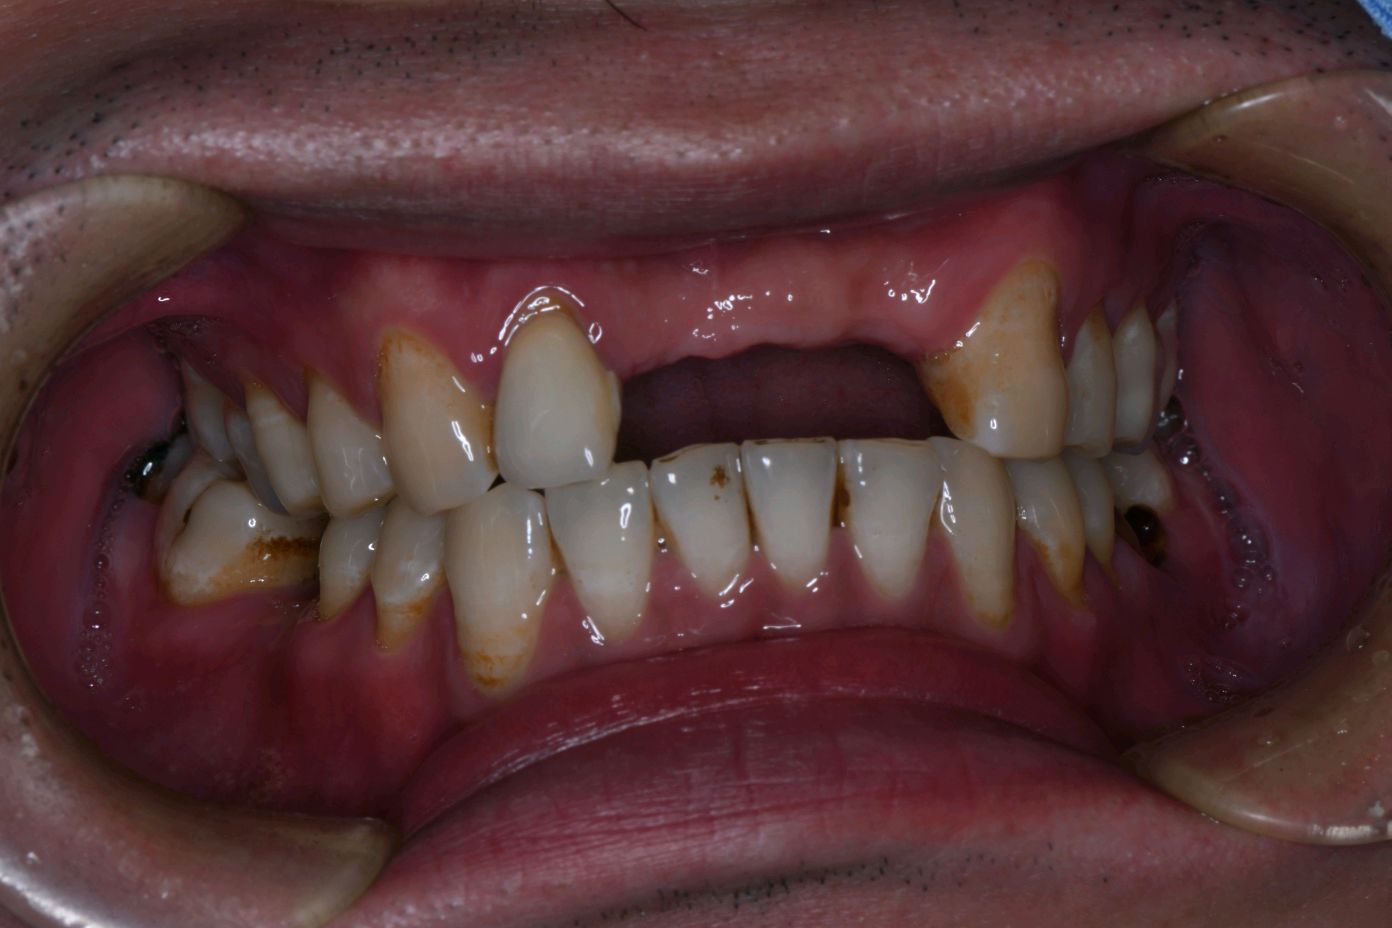

患者男,三十岁,12、11、21缺失。X线示牙槽嵴垂直和水平骨宽度不足。颊侧凹陷缺牙间隙正常。中度萎缩,无骨尖、软组织的增生,牙龈无红肿,角化龈充足。这位患者很符合帐篷钉技术的适应症。通过植入帐篷钉固定植骨材料,给新骨的再生创造了一个稳定的局部环境和生长的空间。最后植入骨粉骨膜及CGF膜,严密缝合。待骨成型即可种植修复。

术前

图片发自160App